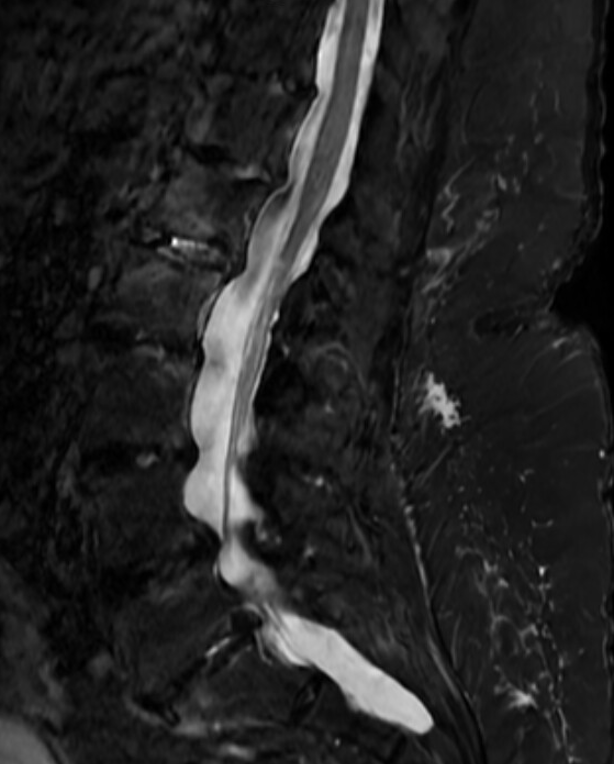

Multiple vascular risk factors, chronic right carotid occlusion, CAHD — presenting with acute bilateral lower extremity weakness. Near-complete recovery after IV t-PA.

Day 1 MRI is normal